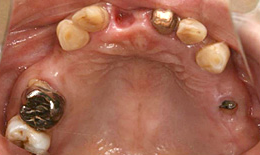

インプラント症例(23) 60歳 女性

- 上顎

- 保存困難な歯を抜歯後、インプラントを5本埋め込んで、セラミックスクラウンを被せた